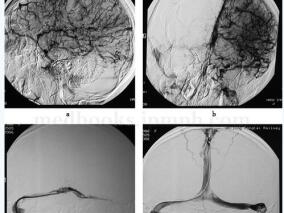

1小时条评论一、病历摘要:患者女性,20岁,主因头痛、呕吐9天,意识障碍5天于2006年7月30日以静脉窦血栓形成收入神经内科重症监护病房(N‐ICU)。患者入院前9天外出游玩回家后感头痛,随后呕吐10余次,进食后明显,不伴发热、精神异常、肢体活动障碍等。按中暑口服药物未见明...